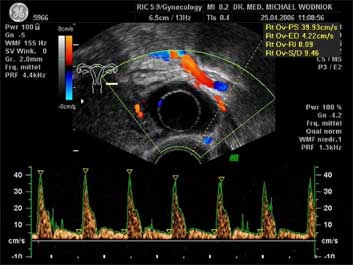

Ultraschall des kleinen Beckens mit der Vaginalsonde Die Ultraschalluntersuchung ist ein bildgebendes Verfahren, welches die Reflektion oder Echos von Ultraschallwellen in den unterschiedlichen Geweben und Organen ausnützt um computergestützt Schnittbilder aus dem Inneren des Körpers zu erstellen. Durch moderne hochleistungsfähige Mikroprozessoren ist es in den letzten Jahren möglich geworden, auch 3-dimensionale oder sogar bewegte 3-dimensionale (4-D) Bilder bzw. Bildsequenzen zu erzeugen. Beides können wir Ihnen in der Praxis anbieten. Eine Ultraschalluntersuchung ist ungefährlich und schmerzfrei. Durch die Anwendung von Dopplerverfahren, mit welchen wir den Blutfluss in den Organen feststellen und messen können, erweitern wir die Untersuchung um die funktionelle Dimension. Ein weiterer Bestandteil unseres Leistungsspektrums ist die farbkodierte Dopplersonographie. Farbkodiert sind entweder die Richtung des Blutflusses oder dessen Intensität. Über die computergestütze Berechnung des Blutflusswiderstandes ist im Einzelnen eine Aussage bzw. Vorhersage über die qualitative und quantitative Durchblutung möglich. (Plazentadurchblutung, kindliche Blutgefässe, Durchblutungsmuster bei verschiedenen Tumoren des Unterleibes und der Brustdrüsen) Ultraschalluntersuchungen haben in unserem Fachgebiet vielfältige Anwendungsmöglichkeiten gefunden. Besonders faszinierend ist der Einsatz im Bereich der vorgeburtlichen Diagnostik. Bereits in der 10. Schwangerschaftswoche ist es möglich, die Extremitäten des Embryos darzustellen und Aussagen zum Körperumrissbild zu machen (Ausschluss von Spaltbildungen, Nackentransparenzmessung). Auch im Bereich der Gynäkologie ist die Bedeutung des Ultraschalls stetig gewachsen und hat sich als erweiterte Vorsorge etabliert. Durch die vaginale Ultraschalluntersuchung können bereits kleine Veränderungen entdeckt werden, die sich der manuellen Tastuntersuchung noch entziehen. Auffällige Tastbefunde an den Eierstöcken sind durch den Einsatz von 3D / 4D in Kombination mit der Farbdoppleruntersuchung besser interpretierbar und können dadurch Frauen unnötige abklärende Operation ersparen. Die Anwendung des 3D Ultraschall, insbesondere im Coronarschnitt, lässt eine effektive Beurteilung für Veränderungen (Polypen, Karzinome) der Gebärmutterschleimhaut zu. ![]() ![]() ![]() ![]()